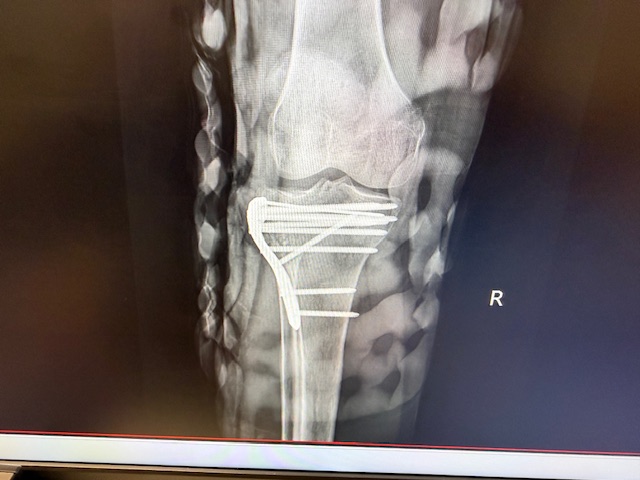

The diagnosis was a fractured tibia plateau – fancy medical words for a broken leg. On September 5 surgery was performed to realign and elevate the knee cap, and to insert a total of 10 metal screws!

Great to hear you are all back to boating. Looking at your knee reminds me of Capt Rick’s installation of the Heather Handrail on Bushranger. I think Capt Rick is neater!